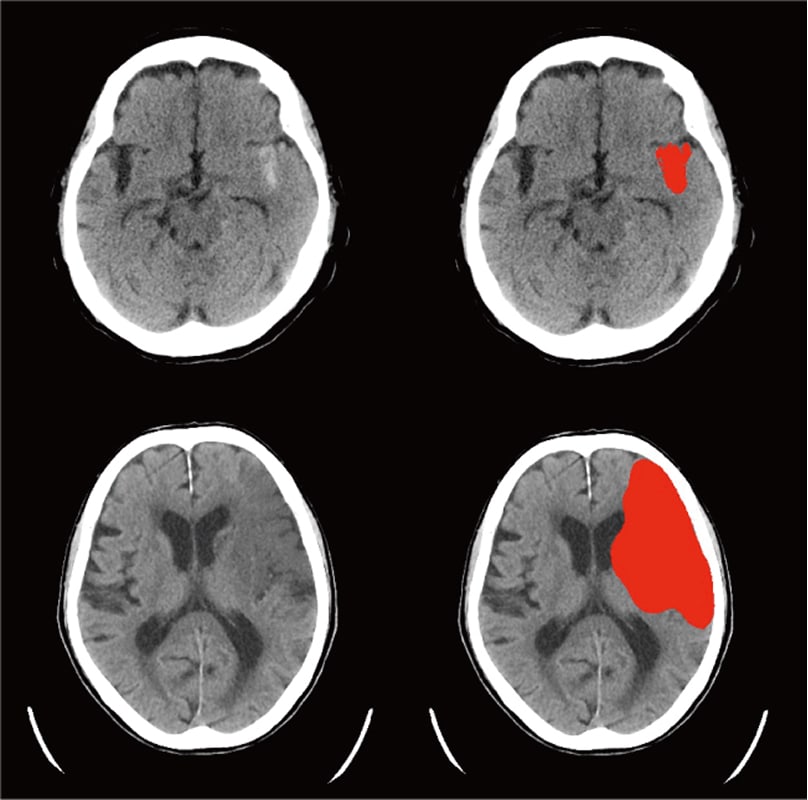

頭部CT画像から

頭蓋内の高吸収領域を自動抽出

頭部単純CTの画像情報から、頭蓋内の高吸収領域を抽出し強調表示をおこないます。各スライスの高吸収領域が色付けされて表示されます。